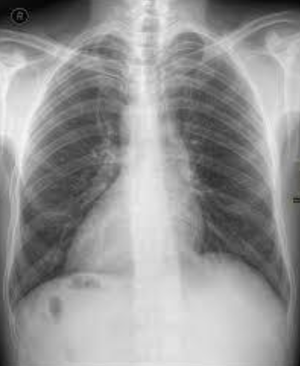

Situs inversus. The apex of the heart is on the right side (dextrocardia). The gastric air bubble is also on the right. So basically everything is flipped on to the opposite side. and moreover the left hemidiaphragm is at a higher level than the right one. can be due to the liver on left side. woa!!!!

Exactly @CHANDAN. (Sinus inversus Totalis) Radiological Finding: The Heart is seen on the right side of the thorax mainly and apex pointing to the right The right Cardiac border is composed of pulmonary artery, left atrium and left ventricles The left cardiac border is composed of right atrium The abdominal viscera: Gastric air bubble is seen on the right side and liver shadow on the left side. Diagnosis Dextocardia (Situs Inversus Totalis): Cardiac displacement or dextroposition due to lung pathology.

I think this is not a case of Dextrocardia/Situs Inversus as in case already mentioned AP view of Chest X ray